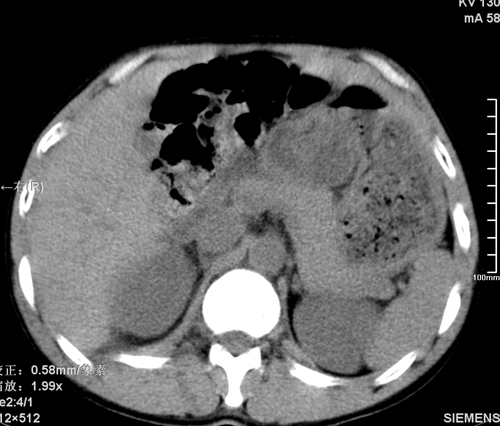

以下是引用qiushi在2008-3-28 12:00:00的发言:[br]腹膜后血肿,所见腰椎横突骨折.[br]建议上传骨窗、腰椎扫描.

以下是引用tao772在2008-3-28 12:29:00的发言:[br]右侧腹膜后积血,右侧腰大肌挫伤,右侧部分横突骨折. 肾脏最好报一下挫伤,必要时增强。